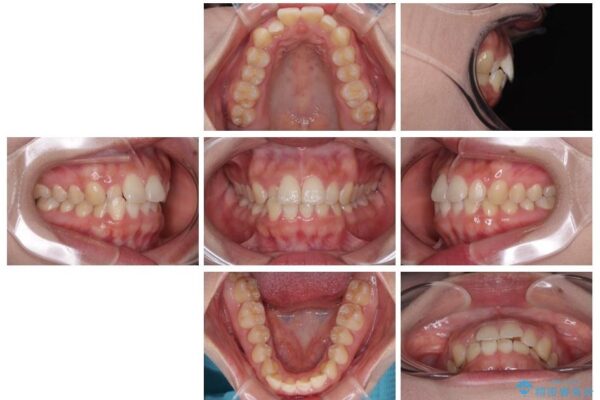

前歯のデコボコが気になるでのことで来院された患者様です。

歯列アーチが狭くスペース不足により前歯がデコボコしている状態でした。見た目を改善しつつ、前歯を前方に突出させず、自然な笑顔を目指したいというご希望でした。

治療前

• 目立ちにくい表側装置で1年完了!狭いアーチを側方拡大し前歯のデコボコを整えた症例 治療前画像